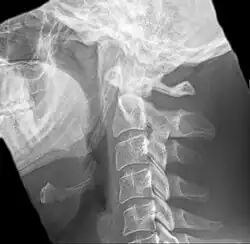

Radiograph, lateral view showing joint-like formation in ossified stylohyoid ligament -

Diagnosis is suspected when a patient presents with the symptoms of the classic form of "Eagle syndrome" e.g. unilateral neck pain, sore throat or tinnitus. Sometimes the tip of the styloid process is palpable in the back of the throat. The diagnosis of the vascular type is more difficult and requires an expert opinion. One should have a high level of suspicion when neurological symptoms occur upon head rotation. Symptoms tend to be worsened on bimanual palpation of the styloid through the tonsillar bed. They may be relieved by infiltration of lidocaine into the tonsillar bed. Because of the proximity of several large vascular structures in this area this procedure should not be considered to be risk free.

Imaging is important and is diagnostic. Visualizing the styloid process on a CT scan with 3D reconstruction is the suggested imaging technique.[13] The enlarged styloid may be visible on an orthopantogram or a lateral soft tissue X ray of the neck.